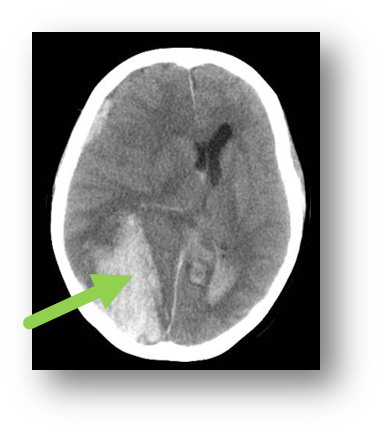

Q

subdural hematoma